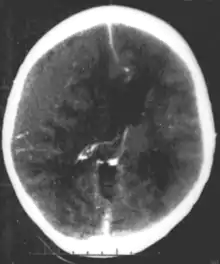

عفونتهای سیستمیک میتواند در نتیجه عواقب عصبی تکوینی زمانی که آنها در دوران نوزادی و کودکی انسان رخ میدهند باشند، اما نمیتواند به عنوان یک اختلال عصبی تکوینی اولیه شناخته شوند، به عنوان مثال HIV[14]، عفونتهای سر و مغز مانند آبسه مغز، مننژیت یا آنسفالیت، شانس بالای رخداد مشکلات تکوینی و در نهایت یک اختلال را دارا هستند.

تعدادی از بیماری های عفونی میتوانند به صورت مادرزادی (قبل و یا در هنگام تولد) منتقل شوند و همچنین میتواند باعث مشکلات تکوینی جدی گردند، به عنوان مثال ویروس HSV ،CMV، سرخچه (سندرم سرخچه مادرزادی)، ویروس زیکا، و یا باکتریهایی در سیفلیس مادرزادی که اگر درمان نشوند ممکن است به عصبی سفلیس پیشرفت کنند. همچنین تک یاخته مانند پلاستمودیوم و یا توکسوپلاسما میتواند باعث توکسوپلاسموز مادرزادی شوند، که با چند کیست در مغز و سایر ارگانها منجر به انواع مشکلات عصبی میگردند.